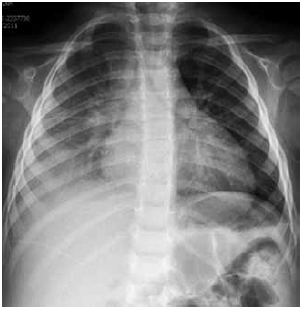

Criança de 1 a 5 m dá entrada no pronto atendimento com história de febre há 5 dias e cansaço hoje. Ao exame físico apresenta: regular estado geral, descorada+, hidratada, acianótica, anictérica, sonolenta, taquidispneia moderada (batimento de asa de nariz e retração intercostal), FR-50, FC-130, PA 80 x 50, Sat 88% em ar ambiente, pulsos firmes (central e periférico) e tempo de enchimento capilar – 2 segundos. Ausculta pulmonar: murmúrio vesicular presente bilateralmente, bastante diminuído em base direita, e com estertoração creptante à direita. A criança foi colocada na sala de emergência, monitorizada, ofertado oxigênio em máscara com reservatório, sem reinalação, 15 litros de oxigênio/min com melhora da saturação – 100%. Obtido acesso venoso periférico, e coletados exames: hemograma, PCR, hemocultura e solicitado radiografia tórax no leito.